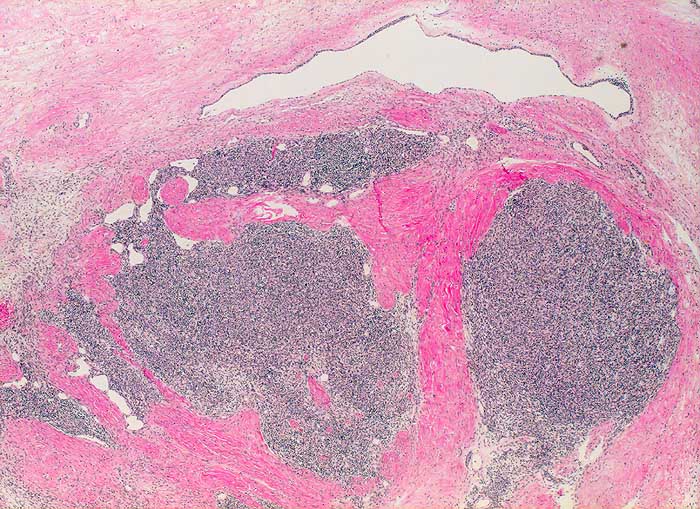

Thymom (Typ A nach WHO)

Der zytologische Befund von epithelialen Thymustumoren ist abhängig vom histologischen Subtyp. Die Einteilung der Thymome nach WHO umfasst die Typen A, AB, B1, B2, B3 und Typ C (Thymuskarzinom). Die Subtypen unterscheiden sich bezüglich Morphologie und Atypiegrad der epithelialen Zellen und in der Menge der beigemischten unreifen T Lymphozyten. Unten gezeigt wird ein Thymom vom Typ A (medulläres Thymom). Die Ausstriche enthalten bei diesem Subtyp monotone Spindelzellen mit feingranulierten Kernen ohne Atypien und nur wenige Lymphozyten. Ein Teil der Spindelzellen kann positiv sein für den B-Zell Marker CD20. Die unreifen T-Lymphozyten sind positiv für CD1a, CD99 und TdT.